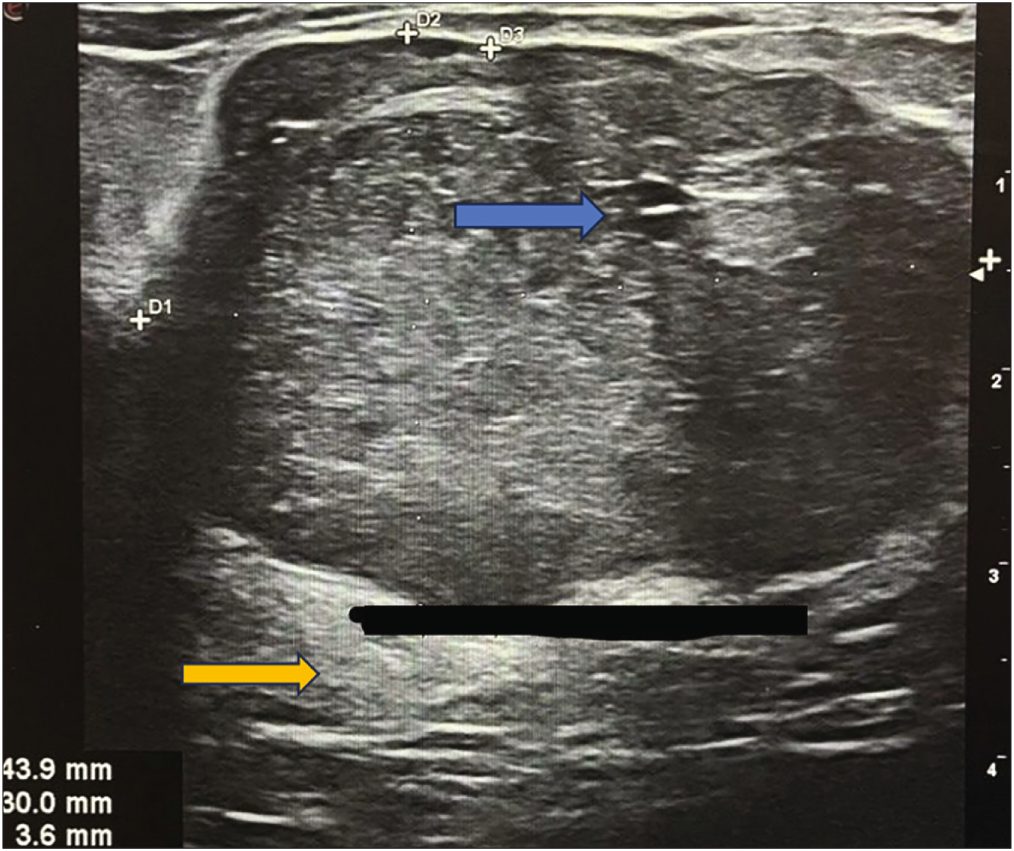

TNBC can present as a rounded circumscribed mass with posterior enhancement, which are features of benign tumors. Figure 5a shows a well-circumscribed solid cystic mass with posterior acoustic enhancement. BIRADS 4C category was assigned by USG on the basis of the sudden increase in size of the lesion and the presence of suspicious ipsilateral lymph nodes. The lesion came out to be invasive ductal carcinoma, grade 3, TNBC. Figure 6 shows a similar oval-shaped mass lesion with circumscribed margins, internal cystic spaces, and posterior enhancement. Due to the chronicity of the lesion and absence of suspicious lymph nodes, a BIRADS category of 4B was assigned on USG. The lesion turned out to be a benign phyllodes tumor on histopathological examination (HPE).

- A 37-year-old female presented with a lump in her left breast for 5 years. A grayscale USG of the left breast shows a parallel-oriented oval-shaped lesion with circumscribed margins, heterogeneous echotexture, and posterior enhancement (yellow arrow). Small internal cystic spaces are seen (blue arrow).